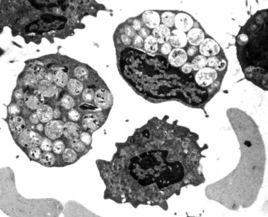

黑蒙性家族痴呆症,又稱台-薩氏綜合徵(Tay-Sachs diesease)。溶酶體缺少氨基己糖酯酶A(β-N-hexosaminidase),導致神經節甘脂GM2積累,影響細胞功能,造成精神痴呆,2~6歲死亡。

溶酶體的酶 分類概述 按功能階段分類 功能作用 形成過程diesease):又叫黑蒙性家族痴呆症,溶酶體缺少氨基已糖酯酶A(β-N...。屬常染色體缺陷性遺傳病,患者多為小孩,常在兩周歲以前死亡...